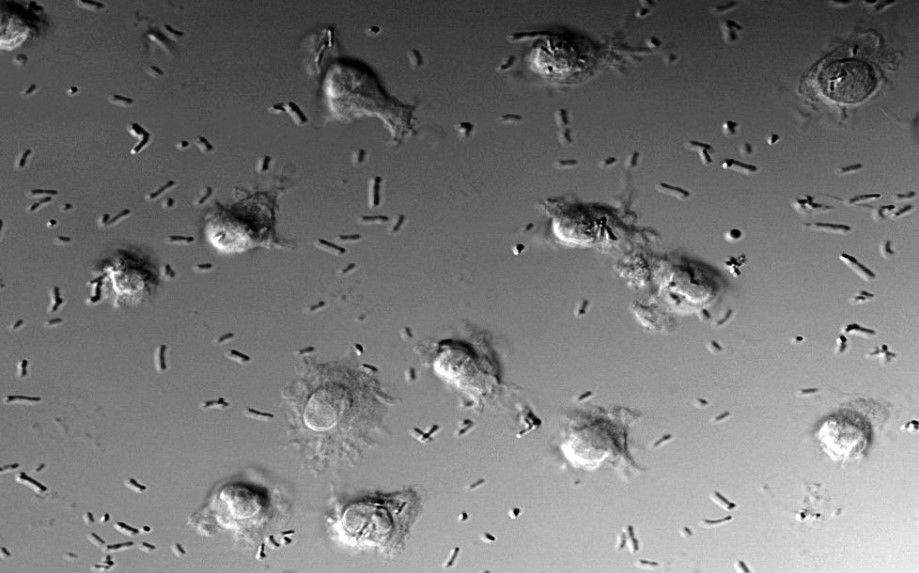

En concreto, el equipo científico ha examinado los efectos de seis probióticos en células dendríticas derivadas de monocitos (moDCs). Los investigadores han desarrollado un modelo ‘in vitro' de estas células especializadas, características del sistema inmunitario de los mamíferos, que ya han aplicado en otros estudios sobre procesos que cursan con inflamación intestinal, como es el caso de la enfermedad celiaca, donde la situación funcional de las células dendríticas juega un papel central.

"Nuestra hipótesis es que la forma en que las células dendríticas procesan los probióticos es determinante para que pongan en marcha una respuesta inmunitaria activa de inflamación, en algunos casos, o una respuesta de tolerancia, que en condiciones normales es la habitual", apunta Arranz.

El trabajo encabezado por los investigadores de la UVa aporta una información amplia y valiosa en torno a los probióticos estudiados. "Los resultados ponen de manifiesto que, dependiendo de cómo procesan las células dendríticas a un probiótico o a otro, se obtiene un efecto diferente. Hemos visto que ‘L. rhamnosus', el microorganismo más utilizado, promueve la maduración de las células dendríticas, lo que significa que fomenta la activación de la respuesta inmunitaria, de modo que habría que utilizarlos con cautela, por ejemplo, en aquellos individuos que tienen un proceso inflamatorio en curso. En el caso de ‘L. fermentum', derivado de la leche materna, no induce una activación o maduración de las células dendríticas por lo que es un buen probiótico; al igual que ‘B. lactis', que no solo no induce ninguna maduración, sino que podría tener ciertos efectos aniinflamatorios", detalla Arranz.